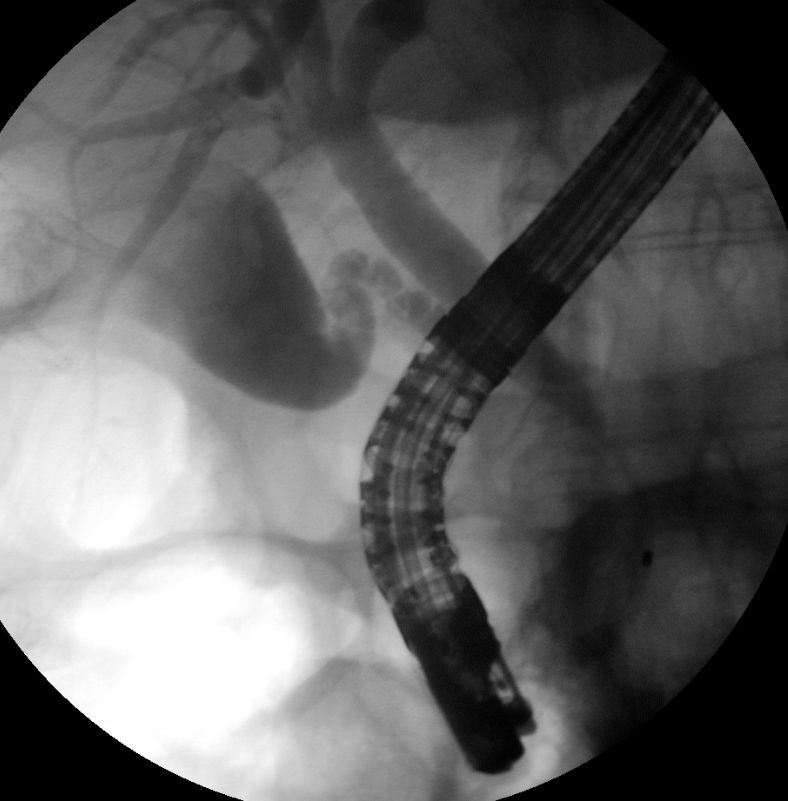

Die ERCP zeigt massiv erweiterte intra- und

extrahepatische Gallenwege. Ein Stent wird gesetzt.![]() |